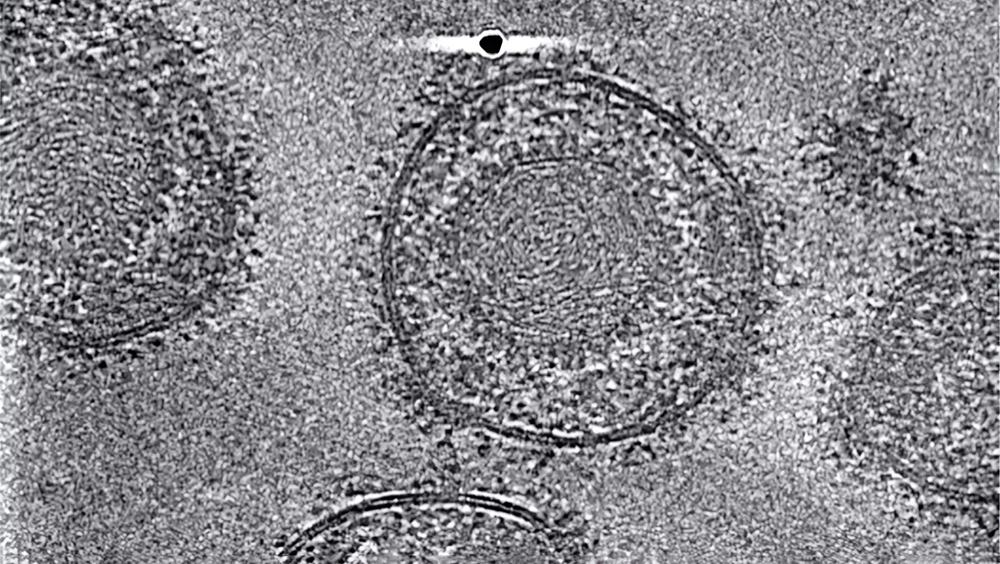

Исследователи из Гамбурга и Геттингена с помощью криоэлектронной микроскопии и компьютерного моделирования рассмотрели белок gB в той форме, в которой он готов объединить вирус и клетку. Это помогло им обнаружить ключевые участки белка, на которые можно воздействовать нанотелом.